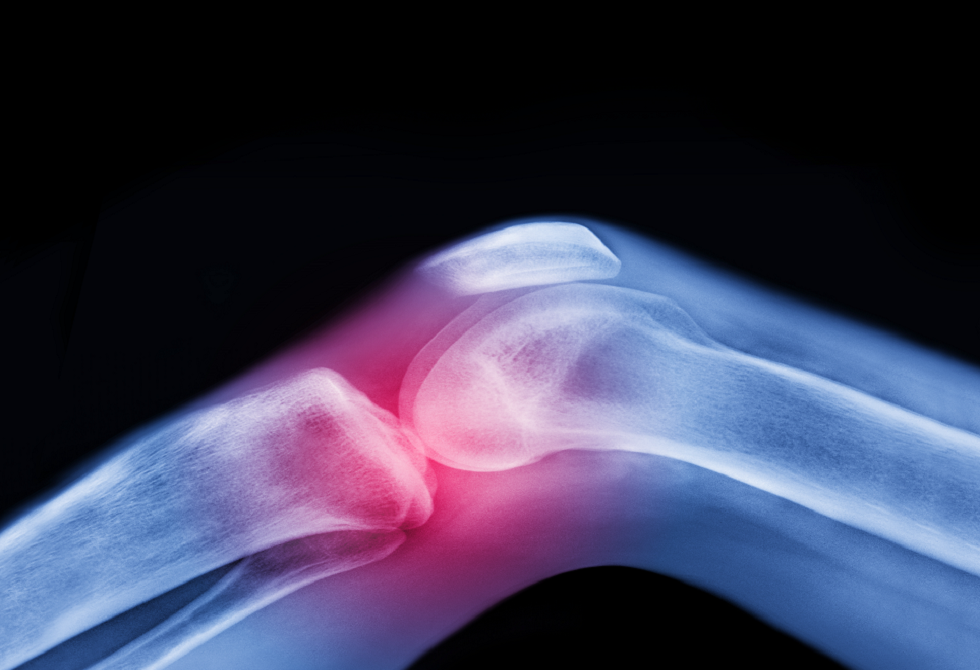

ابتكار جديد يتيح زراعة ركبة بشرية حية لتحسين نوعية حياة مرضى التهاب المفاصل

أعلن باحثون عن تحقيق إنجاز علمي جديد يهدف إلى تحسين نوعية حياة مرضى التهاب المفاصل، من خلال ابتكار ركبة بشرية حية قابلة للزراعة. وأوضح العلماء في جامعة كولومبيا أن هذا الابتكار يعتمد على إنشاء هيكل ثلاثي الأبعاد للركبة باستخدام مواد قابلة للتحلل الحيوي، حيث تمت إضافة خلايا العظام والغضاريف لتجديد الأنسجة.